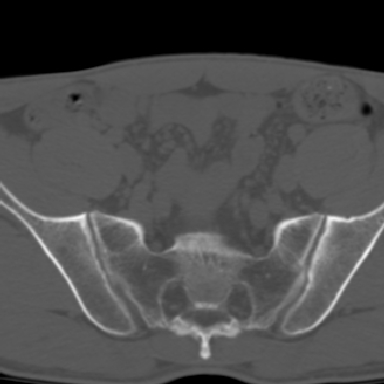

m 30 腰背部不适半年; 清晨时僵硬; 活动症状有所改善

双侧骶髂关节下2/3关节面模糊,毛糙,可见小囊状骨质破坏区.支持强直性脊柱炎.

强直性脊柱炎的早期改变!不仅表现为双侧骶髂关节,第5腰椎与骶椎间的关节突关节也有类似改变。

双侧骶髂关节下2/3关节面模糊,毛糙,髂骨侧可见小囊状骨质破坏区,骶髂关节间隙增宽(软骨破坏期)。支持早期强直性脊柱炎。

双侧骶髂关节下2/3关节面模糊、毛糙,可见小囊状骨质破坏区,呈虫咬状改变,周围可见增生硬化.支持强直性脊柱炎早期表现.

双侧骶髂关节髂骨面硬化,毛糙,小囊变,属于早期强直性脊柱炎